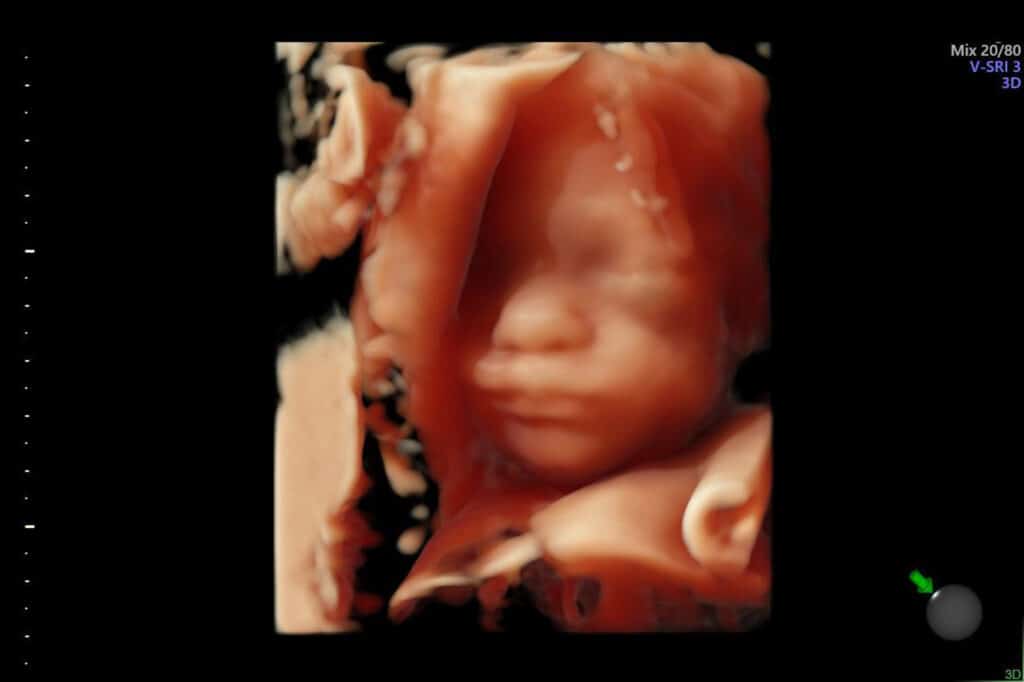

Sages-femmes

Echographistes à Bonneville

Bénédicte PATUREL et Margaux ERRE